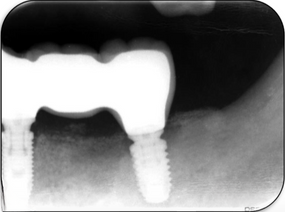

Fig 6: Radiograph at the 2 years review

Three months later, an implant-supported bridge was constructed by our prosthodontist, with ongoing 6-month reviews (Fig 5). Radiographs at the 2-year review confirmed stable bone levels around the implants (Fig 6).